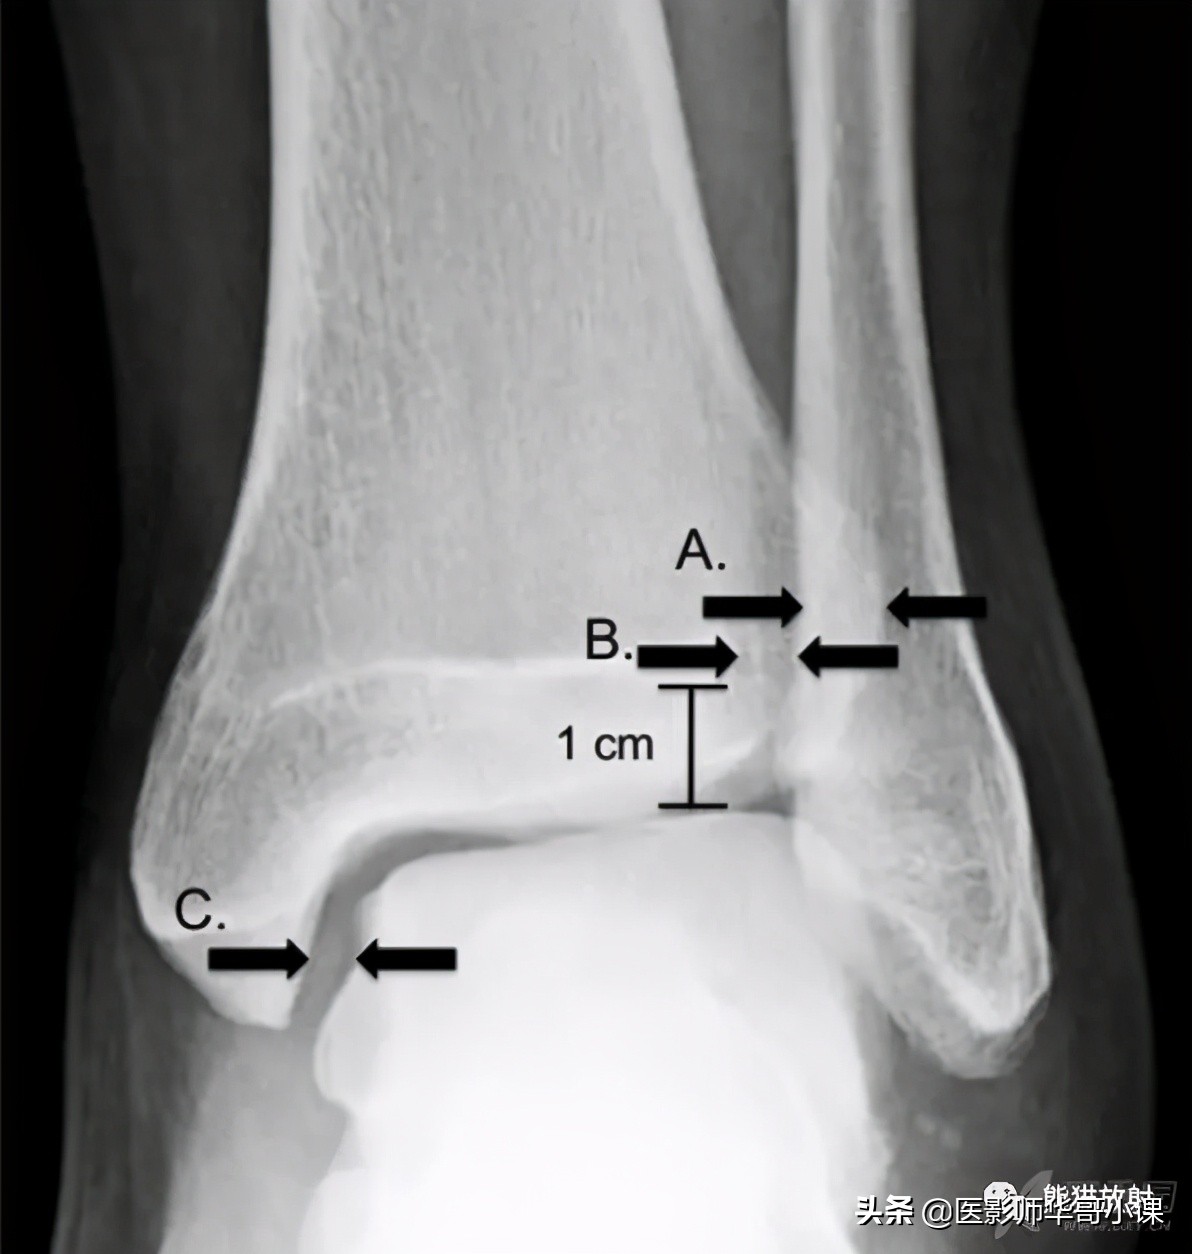

3个影像学检测指标可用于诊断踝关节下胫腓联合损伤 :胫腓骨重叠距离,胫腓间隙(tibiofibular clear space),内侧关节间隙等。

胫骨穹窿上方 1cm 处测量前后位片上胫腓骨重叠大于 6mm,或者踝穴位 X 片重叠大于 1mm 时提示正常,若前后位 X 片上重叠小于 6mm 则提示下胫腓联合损伤。

踝关节内侧间隙的宽度应和胫骨穹窿 / 距骨顶间隙相等或略小。

在负重位或非负重位 X 片上胫腓骨重叠距离减小,胫腓骨间隙或者踝穴内侧间隙增大均提示下胫腓联合损伤。

胫腓骨间隙是影像学上测量最为可靠的指标,因其很少受到下肢和射线成像的角度的影响。CT可以发现 X 片上不明显的骨折;而 MRI 对诊断下胫腓联合韧带损伤具有极高的敏感性和特异性。

胫腓联合损伤诊断测量线 :A、胫腓骨重叠,B、胫腓骨间隙,C、内踝间隙。(其中胫腓骨重叠和胫腓骨间隙的测量在距离胫骨穹窿顶1CM处。)